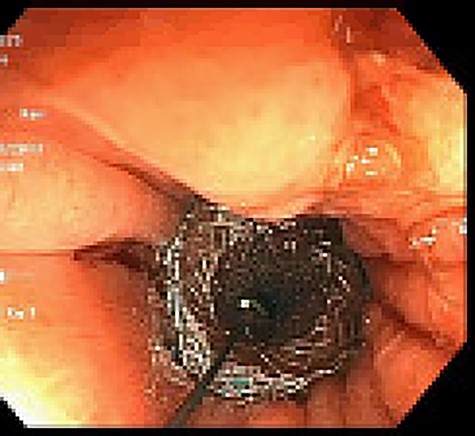

Unfortunately, 6 weeks thereafter he returned with 5-day history of significant abdominal discomfort. He reported tolerance of oral diet without nausea or vomiting. Vitals and laboratory results were unremarkable. However, on computed tomography (CT), initial SEMS had migrated to the transverse colon that herniated into the thoracic cavity via enlarged hiatus (Fig. 6). He underwent upper endoscopy the following morning to ensure the initial stent had not eroded through the gastric conduit into the adjacent colon, as well to ensure adequate positioning of the second stent. Colonoscopy subsequently then proceeded. Although technically difficult the migrated stent was identified and removed with rat-toothed forceps (Fig. 7). His post-procedural course was without complication and he was discharged home the following day with symptom alleviation.

Colonoscopic identification of SEMS within the transverse colon.